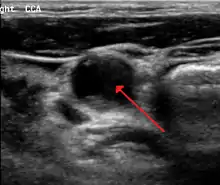

70 percent stenosis of the right internal carotid artery as seen by ultrasound. Arrow marks the lumen of the artery.

Carotid artery stenosis is usually diagnosed by color flow duplex ultrasound scan of the carotid arteries in the neck. This involves no radiation, no needles and no contrast agents that may cause allergic reactions. This test has good sensitivity and specificity.[16]

Typically duplex ultrasound scan is the only investigation required for decision making in carotid stenosis as it is widely available and rapidly performed. However, further imaging can be required if the stenosis is not near the bifurcation of the carotid artery.[17]